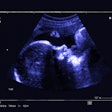

Although breast ultrasound is useful for differentiating masses, the morphologic features of benign and malignant lesions have substantial overlap. Interpretation of these images depends greatly on radiologist experience, leading to the potential for significant interobserver variability, according to the researchers.

As a result, they sought to train a convolutional neural network (CNN) to distinguish between benign and malignant breast masses on ultrasound studies. The researchers retrospectively collected 480 images of 97 benign masses and 467 images of 143 malignant masses for use in training. The deep-learning model, which was developed using the GoogLeNet CNN architecture, was then tested on a set of 120 images of patients with 48 benign masses and 72 malignant masses.